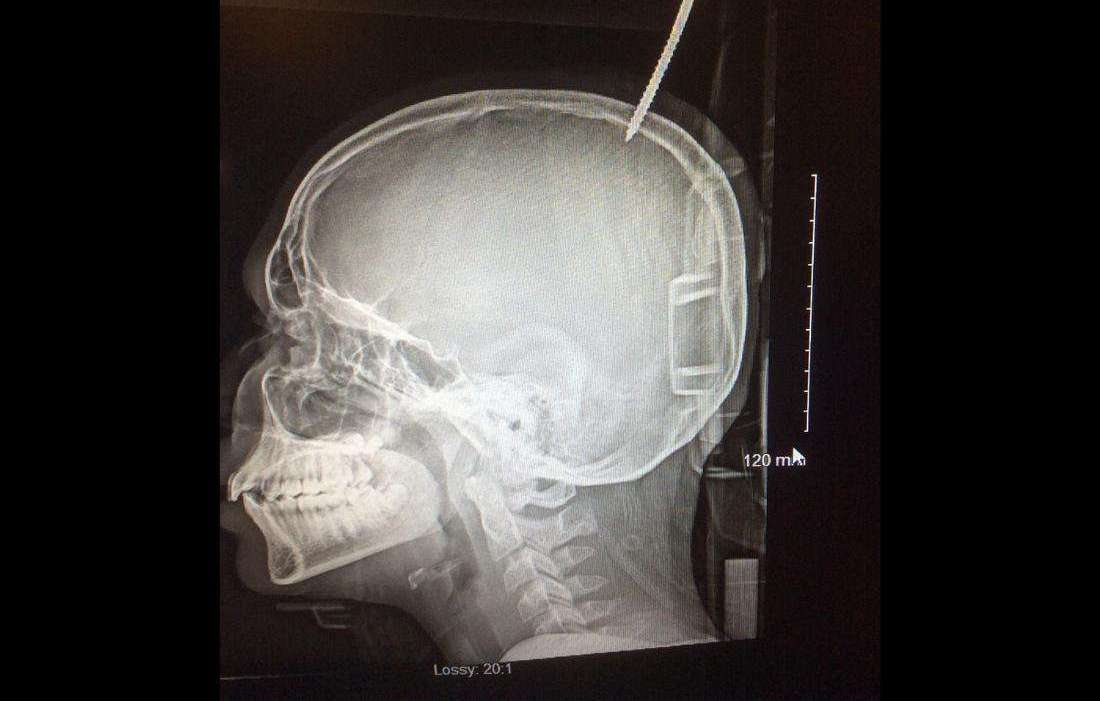

Darius fue trasladado en avión al hospital, donde le tomaron radiografías. Éstas mostraron cuán grave podría haber sido la situación.

De hecho, los rayos X muestran que el tornillo perforó el cráneo de Darius entre las dos mitades del cerebro. Si hubiera sido más profundo, podría haber sangrado. El cirujano afirmó que la lesión habría sido “catastrófica”.